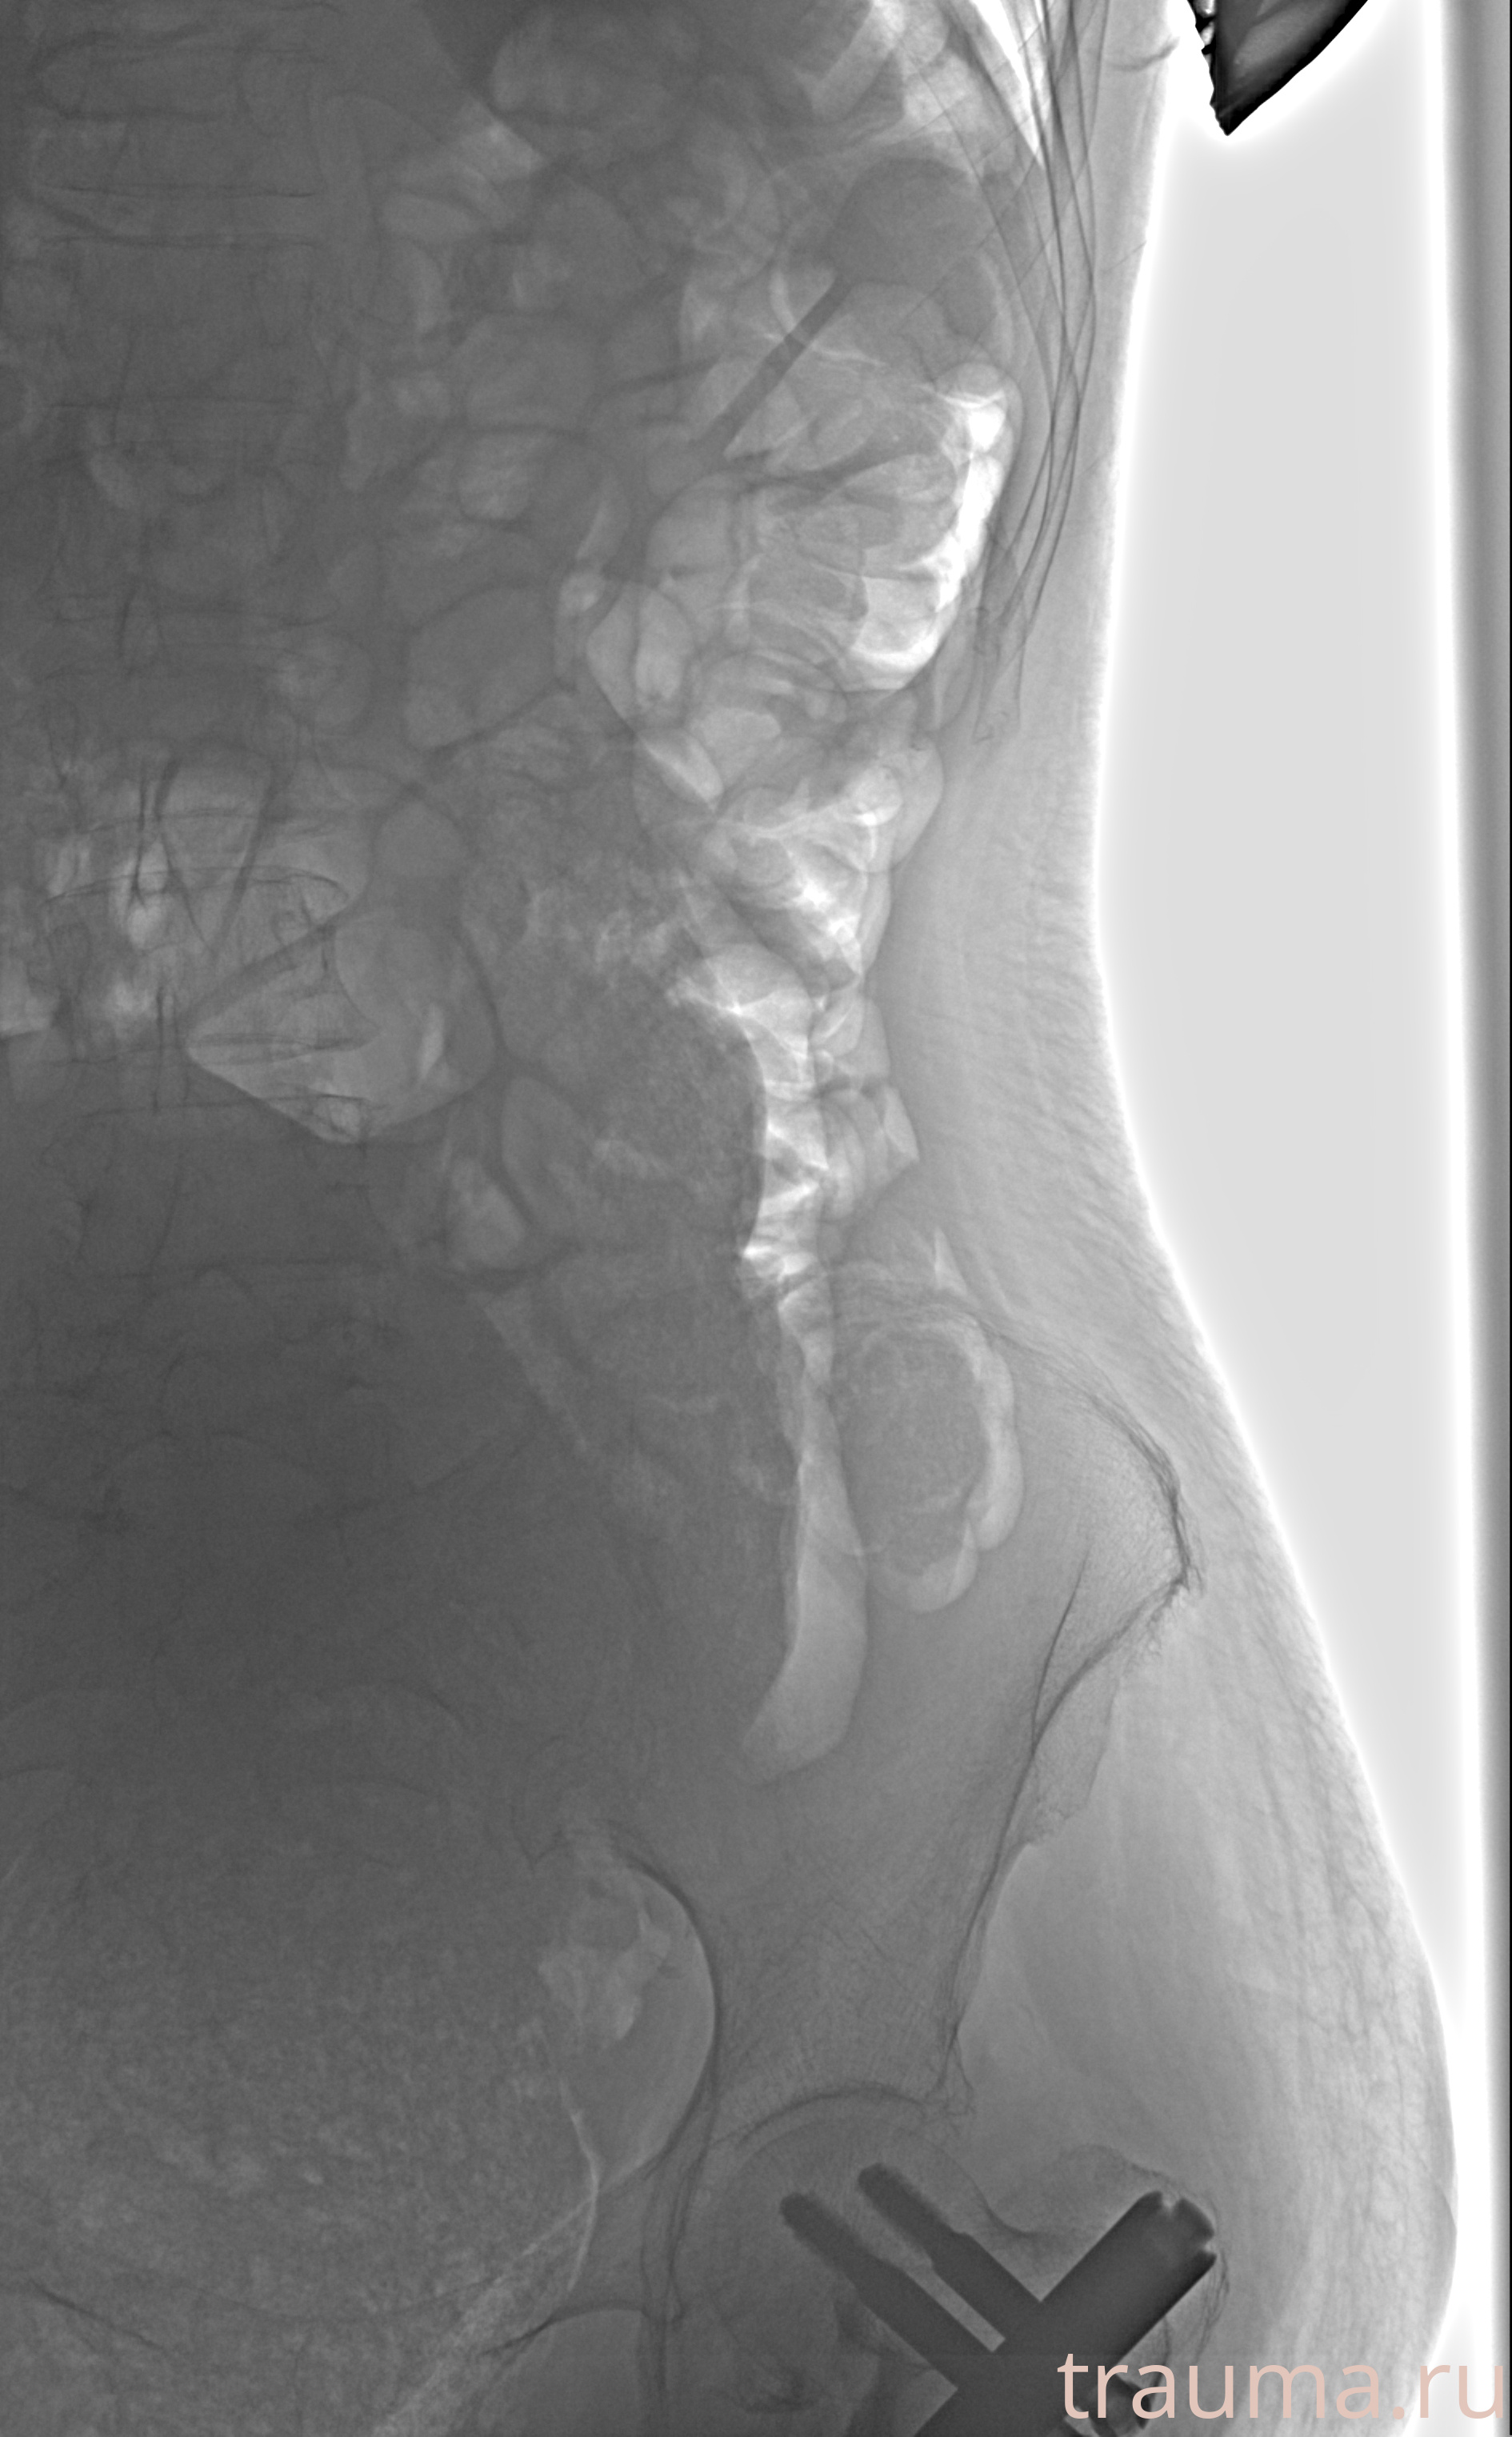

Рентген на дому: по вашему адресу приезжает врач-рентгенолог, травматолог-ортопед с мобильным рентгеновским аппаратом, проводит диагностику травмы или заболевания, делает необходимые рентгенограммы, дает рекомендации по дальнейшему лечению. Получить качественные снимки в домашних условиях возможно благодаря уникальной методике, разработанной МосРентген Центром для института  Склифосовского